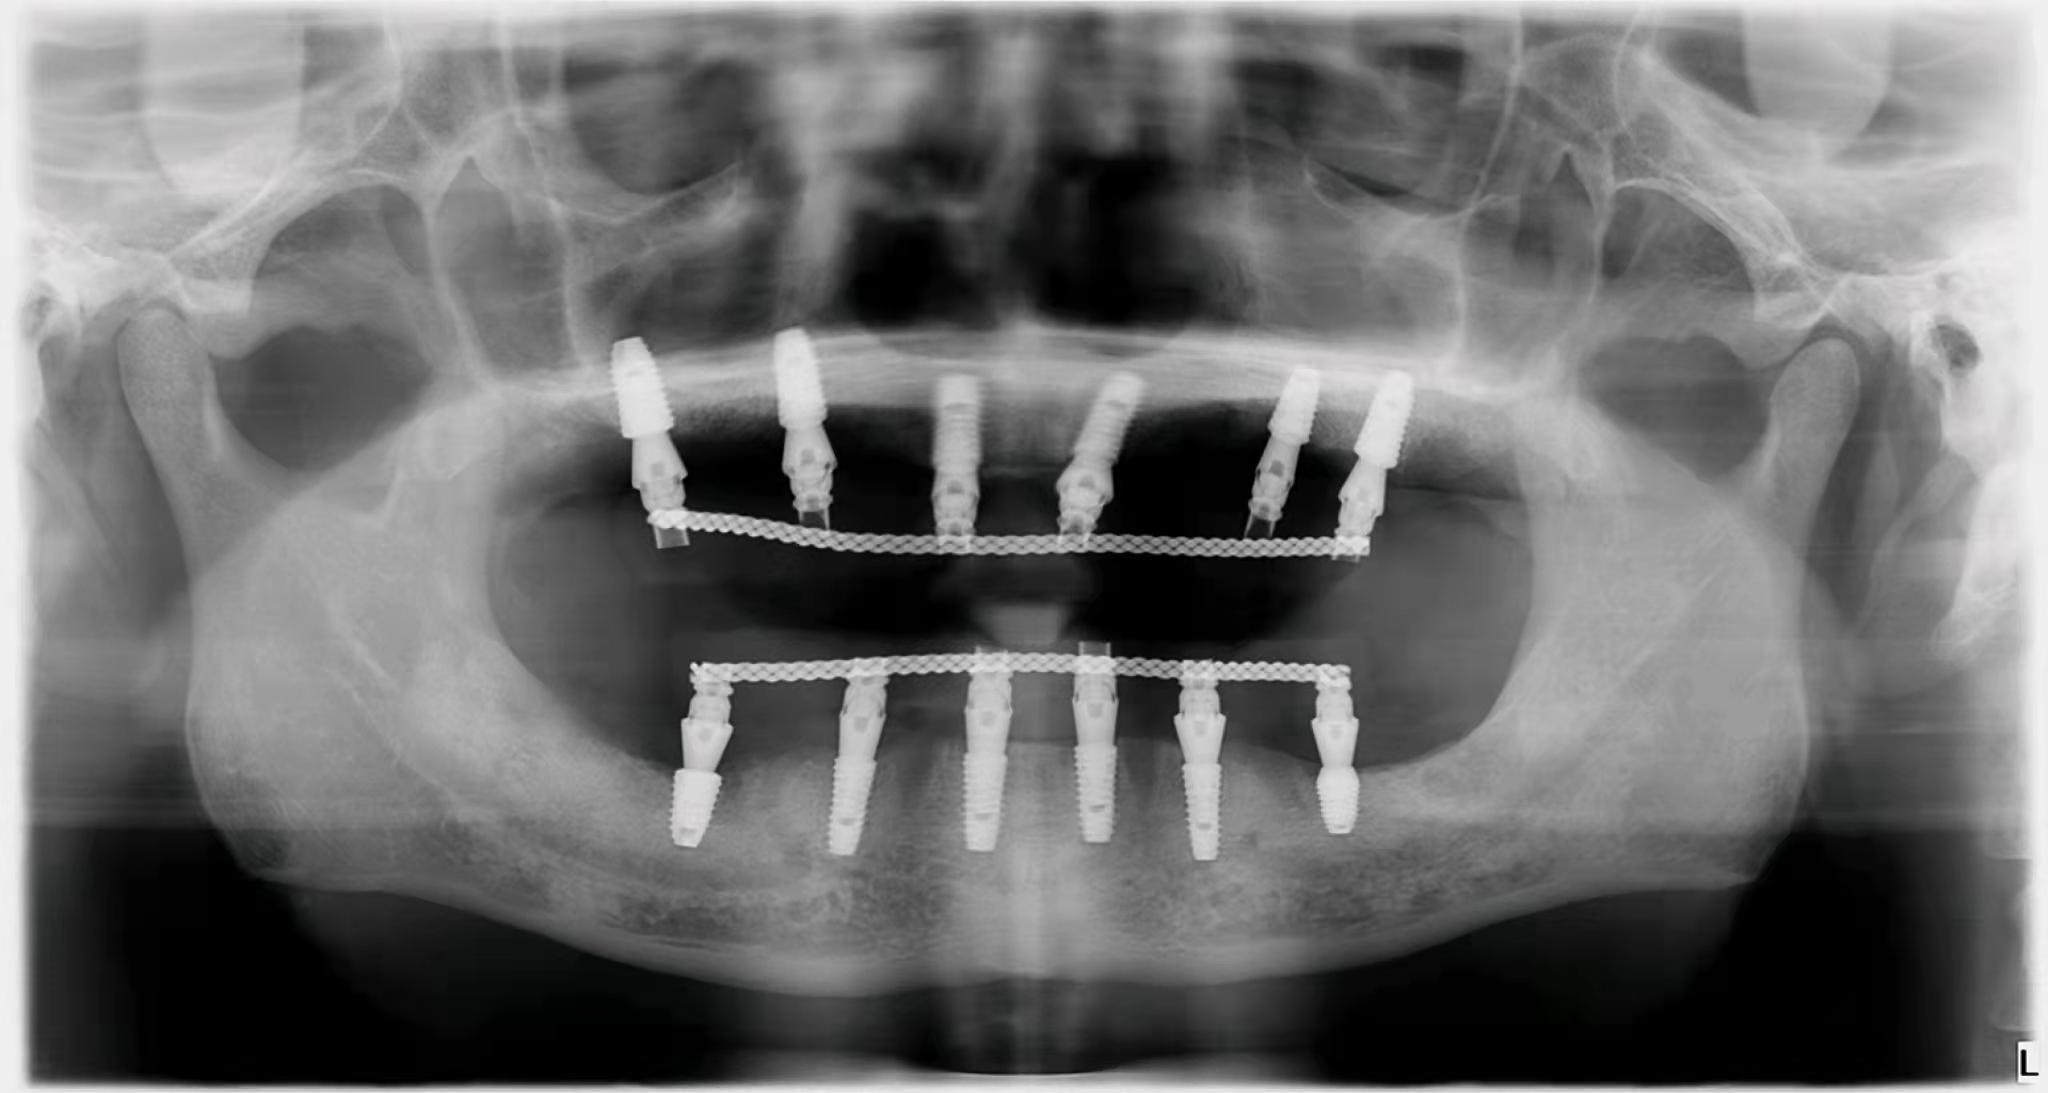

3. 種植牙價格降低在公立和私立口腔中,與種植體不同的是,國內部分牙冠品牌已經被大眾接受。如果是單顆牙缺失,預算有限,可以找醫(yī)生咨詢低成本方案。即使是全口或者半口牙缺失,需要種植,也不需要在牙窩上全部種植,可以用all-one-4,或者all-one-6。